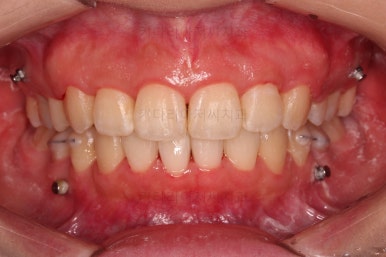

교합, 과개교합 모두 좋아졌고요.

발치 공간도 깔끔하게 닫히고 종료했습니다.

이제 부산무턱교정치과 전후 비교해 볼게요.

웃을 때 튀어나와 보이던 앞니도 많이 개선디ㅗ었고, 치열도 매우 예뻐졌습니다.

옆라인에서도 입술 다물기가 훨씬 편해졌고요.

아래턱에 비해서 나와있던 입술도 뒤로 많이 들어갔고, 턱끝의 방향이 조금 달라지면서 턱이 많이 살아나 보이네요.

전반적으로 만족스러운 치료 결과였습니다.

이상 미니스크류를 이용해 과개교합을 개선하고, 발치교정으로 돌출입과 무턱을 개선한 부산무턱교정치과 치료사례였습니다.